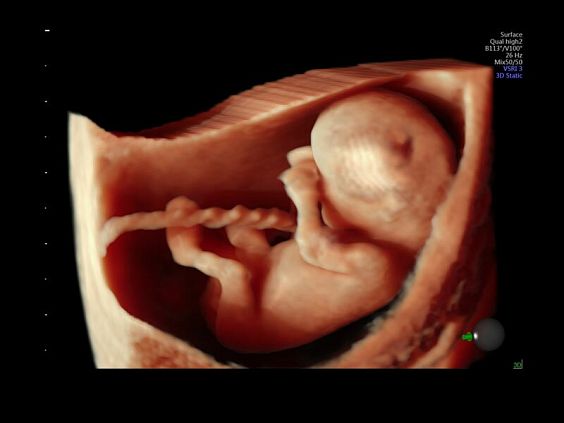

• Автоматическое определение плода в режиме 3D (SonoRenderLive) – позволяет значительно экономить время и получать изображение конечностей и лица плода в режимах 3D без артефактов и помех – система автоматически определяет границы конечностей и лица плода и выстраивает объемное изображение

Современные клинические приложения и высокое качество изображений позволяют использовать Voluson E10 для наблюдения за ходом беременности максимально эффективно. С помощью этого аппарата можно проводить любые исследования, как рутинные, так и комплексные, выявляя проблемы на ранних стадиях и принимая своевременные меры.

Объемное сканирование Voluson — 3D/4D вашей мечты

Объемное УЗИ на Voluson E10 — это не просто потрясающе красивая картинка, это ценный инструмент получения дополнительной информации при обследовании женщин.

Voluson E10 поддерживает инновационные технологии формирования изображений — HDlive Silhouette и HDlive Flow, которые позволяют увидеть мельчайшие детали. Алгоритм SonoRenderlive упрощает рабочий процесс и дает возможность реконструировать изображение поверхностей, определяя область перехода между тканью и жидкостью.

• SonoRenderlive

• Улучшает объемную визуализацию за счет автоматического определения линии начала реконструкции при изображении поверхностей. При исследовании в режиме 4D функция SonoRenderlive непрерывно обновляет положение исходной линии с учетом движений плода.